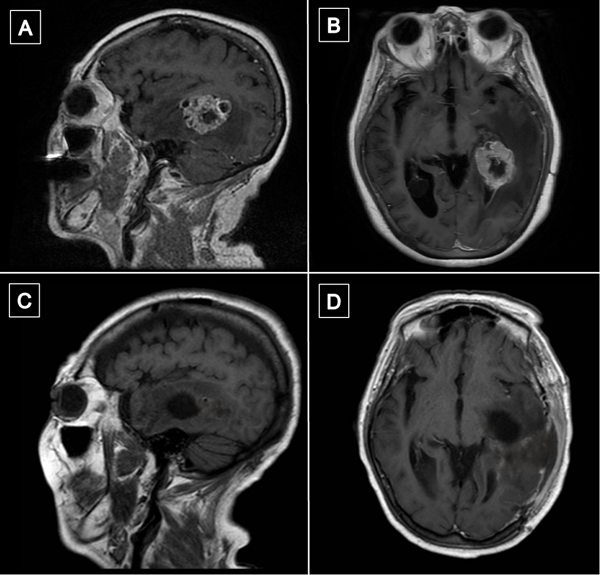

Transcurrido un mes de la cirugía, se realizó resonancia magnética de encéfalo con gadolinio en la que se observó en la región temporomesial izquierda un área de señal líquida con signos de gliosis periférica y sutiles restos de hemosiderina, sin evidencia de lesión tumoral residual. Persistía el edema vasogénico con efecto de masa sobre el sistema ventricular ipsilateral (Figura 6).

Figura 6. Comparación de resonancias magnéticas pre y postquirúrgicas. A y B) RM prequirúrgica de encéfalo, cortes axial y sagital, respectivamente, en secuencia T1 contrastada, se evidencia lesión expansiva con realce heterogéneo localizada en topografía temporomesial izquierda. C y D) RM de encéfalo con gadolinio realizada aproximadamente un mes luego de la intervención quirúrgica. Cortes axial y sagital, respectivamente, en secuencia T1 contrastada en la que se evidencia en región temporomesial izquierda un área de señal líquida con signos de gliosis periférica, sin evidencia de lesión tumoral residual.